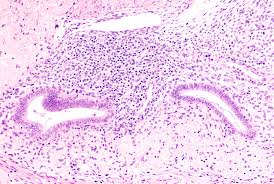

Cancer, symptoms diary, vulva, gynecologic cancer, bloating, inside knowledge: A woman may have a feeling of lower abdominal bloating or a feeling of fullness or mild congestion in the pelvis, both of which can feel just like menstrual symptoms or bowel sluggishness. Ovarian cancer cells can spread to other parts of the body to form secondary cancers, in a process called metastasis. Ovarian cancer australia has produced a symptom diary to help women record any symptoms and talk about their health concerns with their doctor. Ovarian cancer can be difficult to diagnose at an early stage, largely because symptoms can be vague and similar to those of other common illnesses.